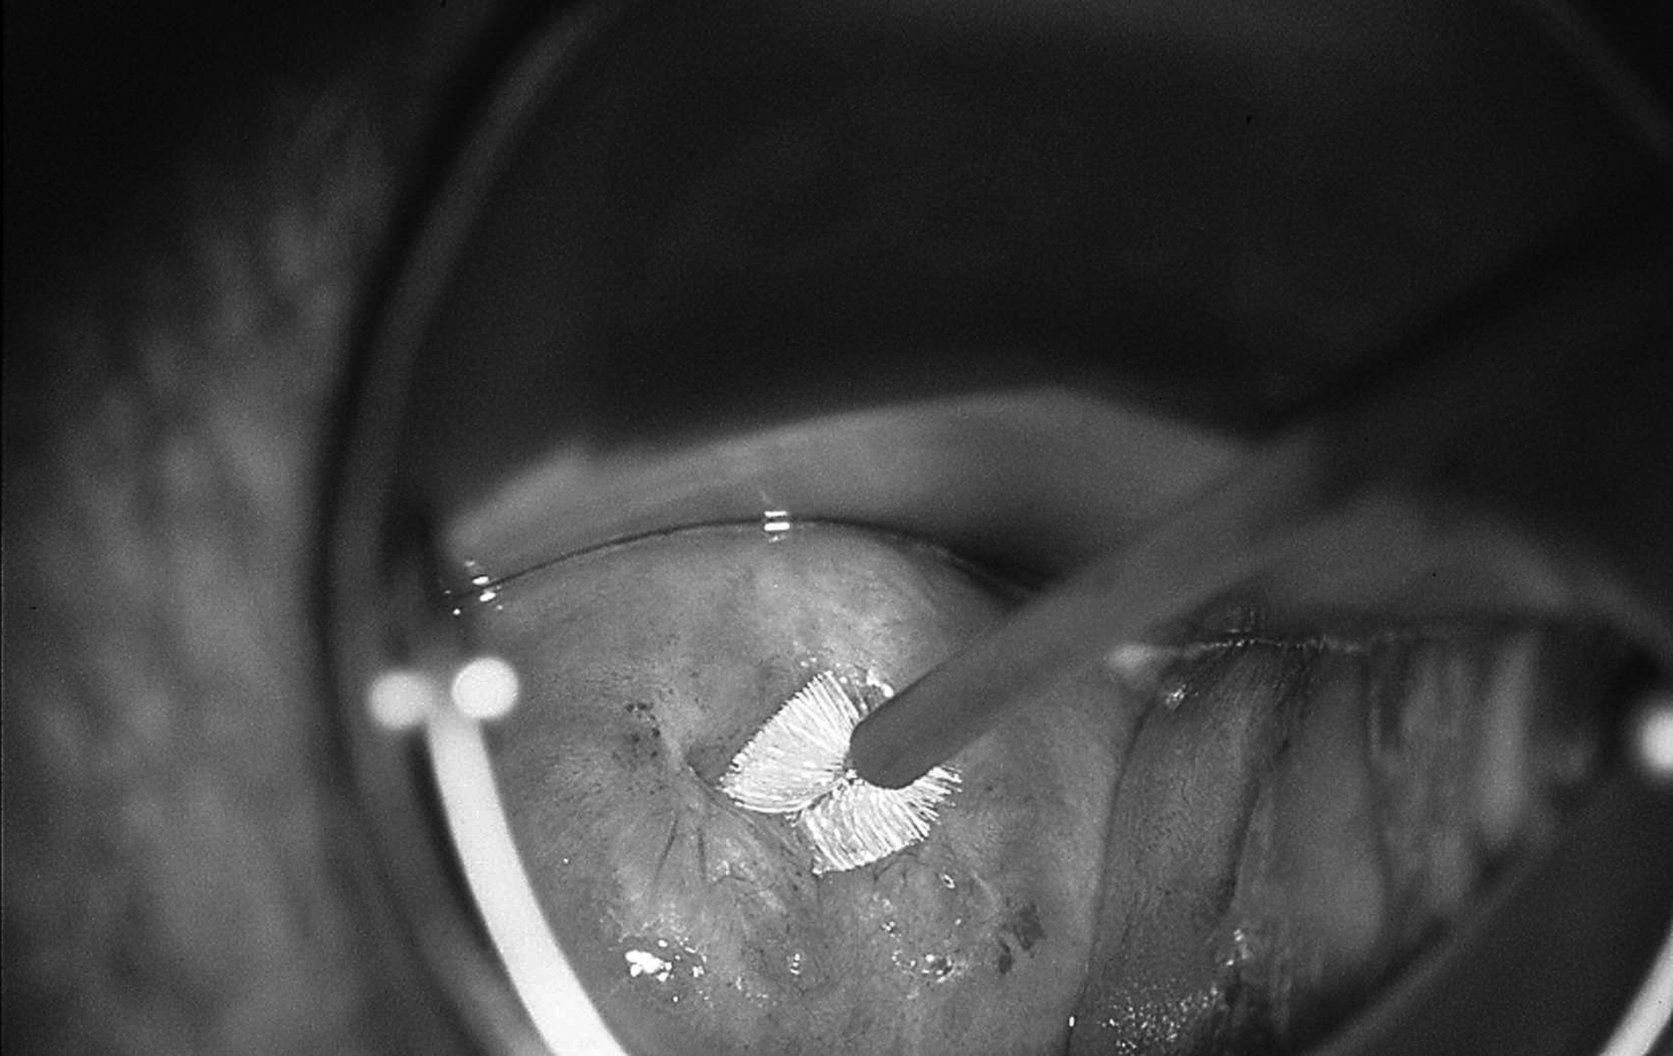

Figure 18.5 Prélèvement du frottis endocervical à l’aide d’une endobrosse

Figure 18.5 Prélèvement du frottis endocervical à l’aide d’une endobrosse.

Cette illustration est également reproduite dans le cahier couleur.